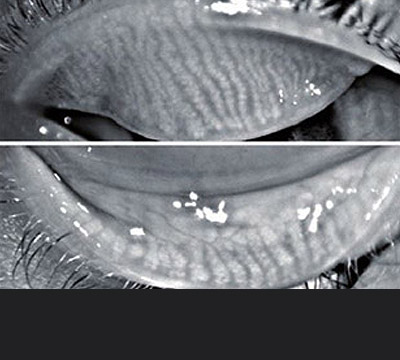

• 마이봄선 검사

마이봄샘 검사: 눈꺼풀 안쪽 기름샘의 구조적 변형과 기능 저하 여부를 정밀하게 분석합니다.